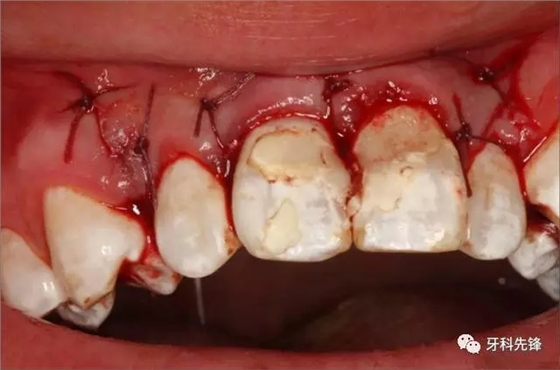

圖14.縫合完畢的口內(nèi)照片

圖13.縫合